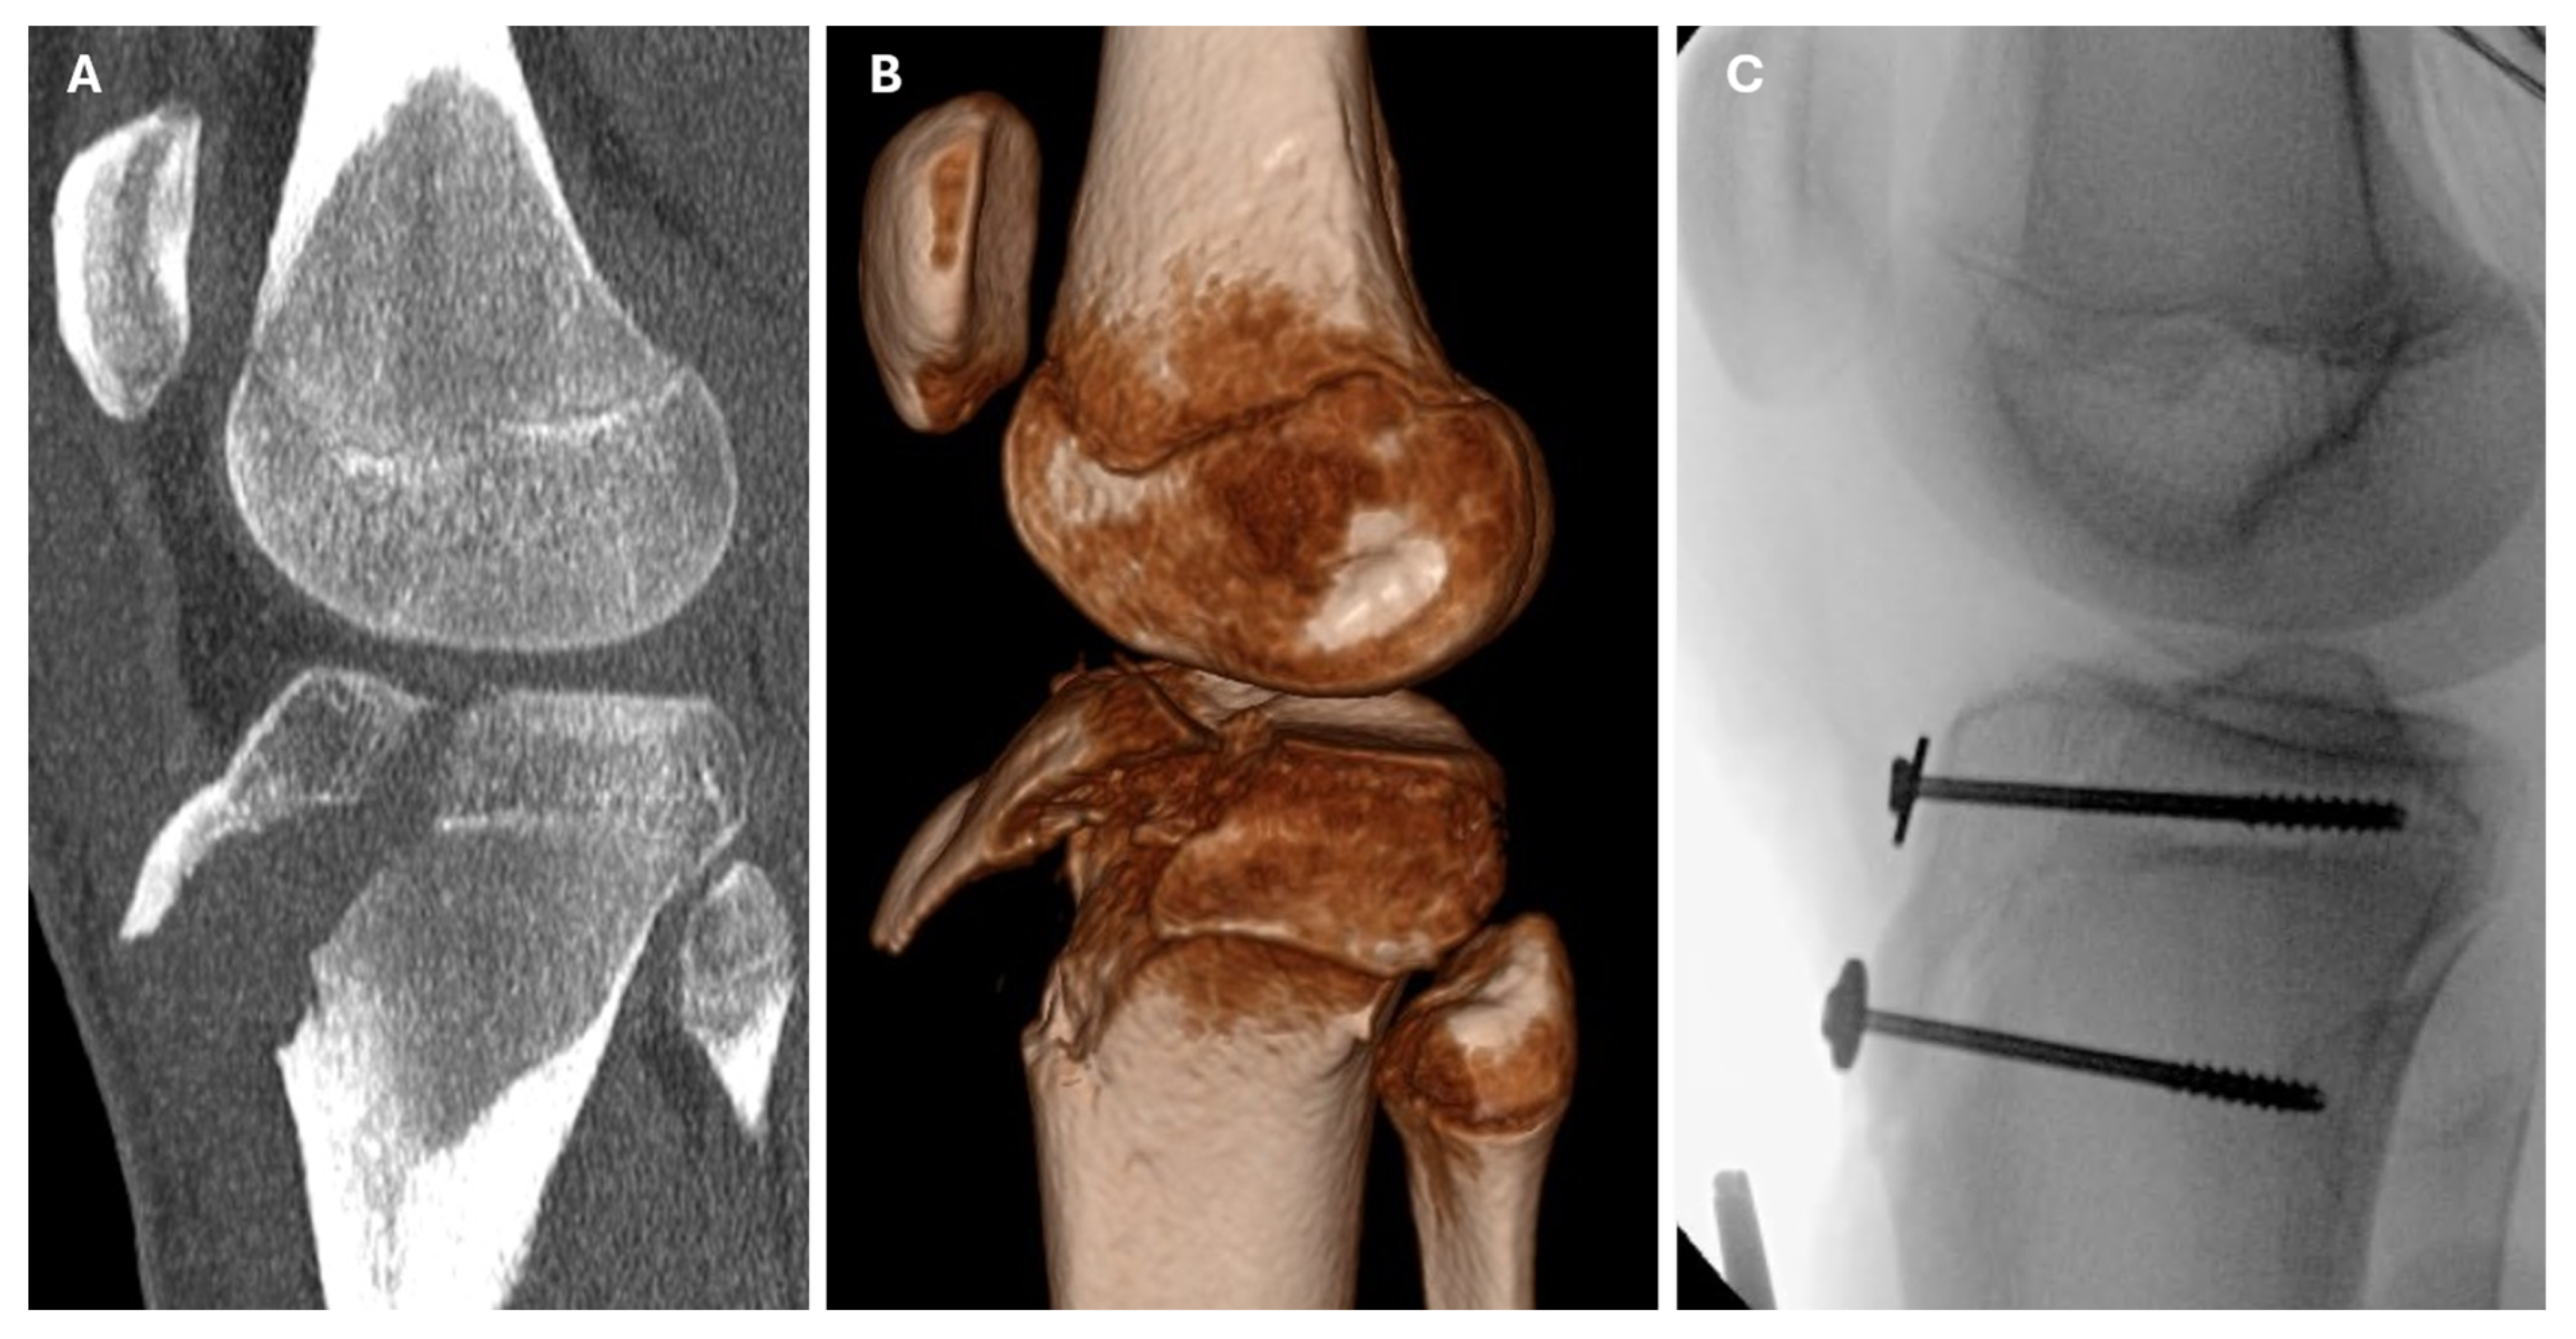

| 7 | Running | CT | IIIa | ORIF | screws | retinacula | - | 18.7 |

| 8 | Athletics | CT | IVa | CRIF | K wires | - | - | 18.4 |

| 12 | Basketball | CT | IVb | ORIF | screws | retinacula, patellar luxation, fibular head fracture | - | 7.3 |

| 16 | Soccer | - | IVb | ORIF | screws | - | - | 10.2 |